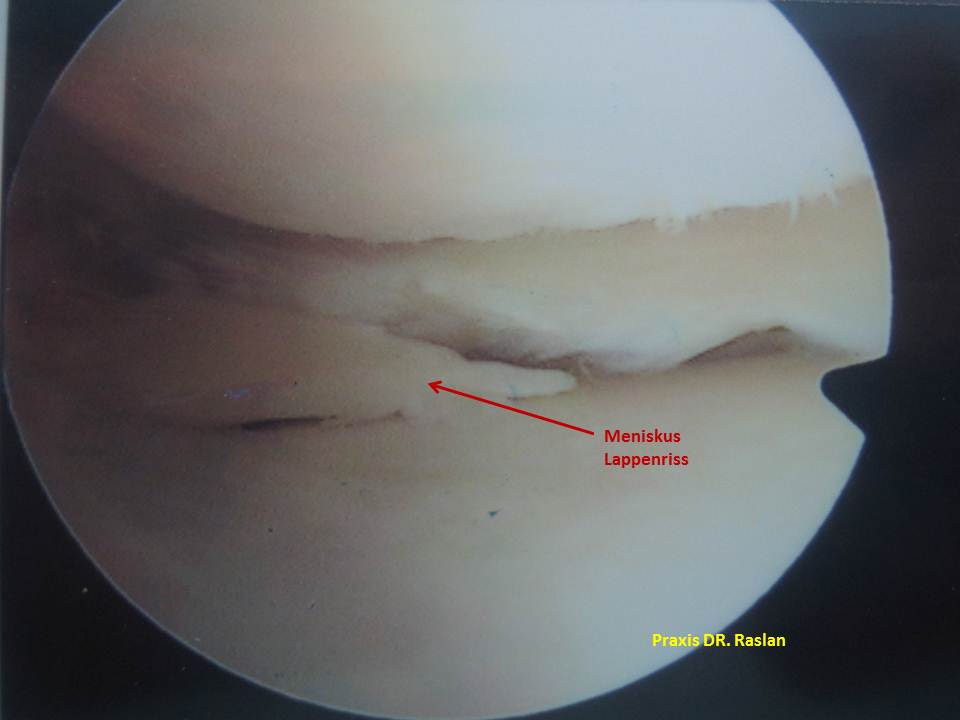

aufgefaserte eingeklemmte Lappenriss Innenmeniskus